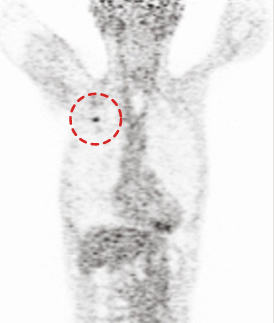

CASE #1 [lung cancer]

15 min (50%) Scan without Denoising

15 min (50%) Scan With Denoising

30 min (100%) Scan Standard